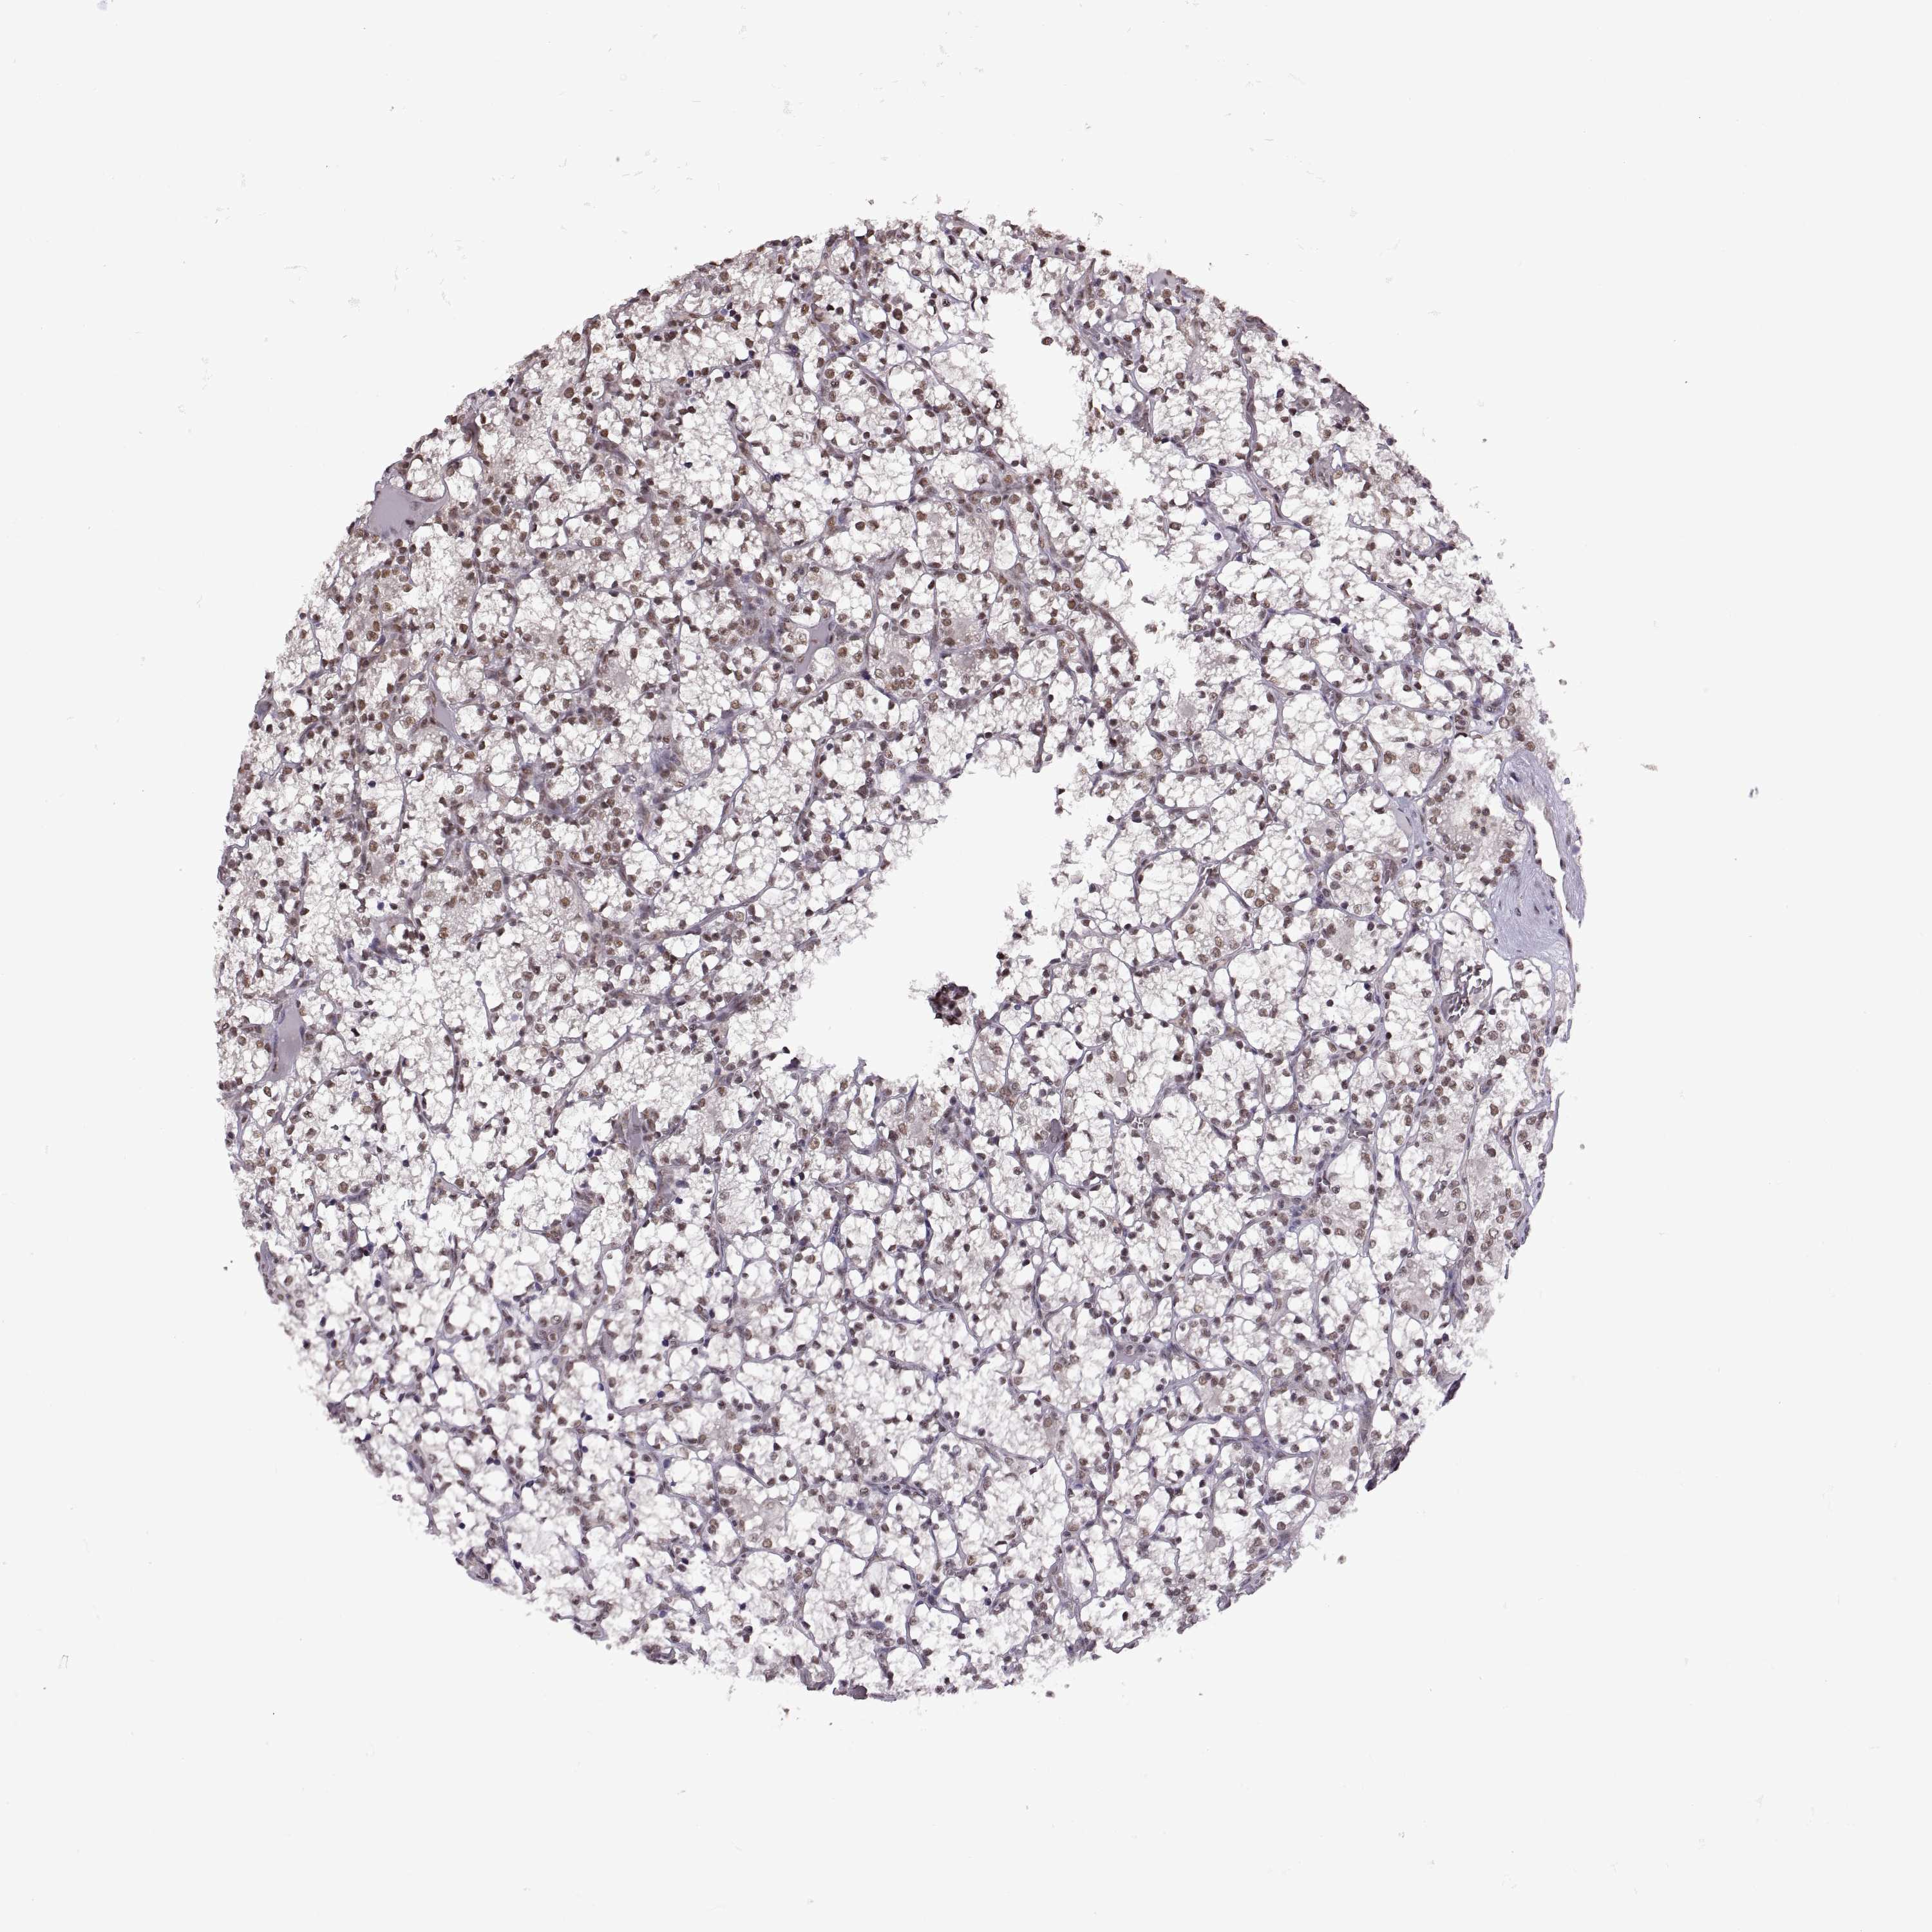

Renal cancer

Kidney renal clear cell carcinoma

KIDNEY RENAL CLEAR CELL CARCINOMA (VALIDATION) - Interactive survival scatter ploti

INTS3 is not prognostic in Kidney Renal Clear Cell Carcinoma (validation)

: 17.13

Average pTPM 13.2

Number of samples 100